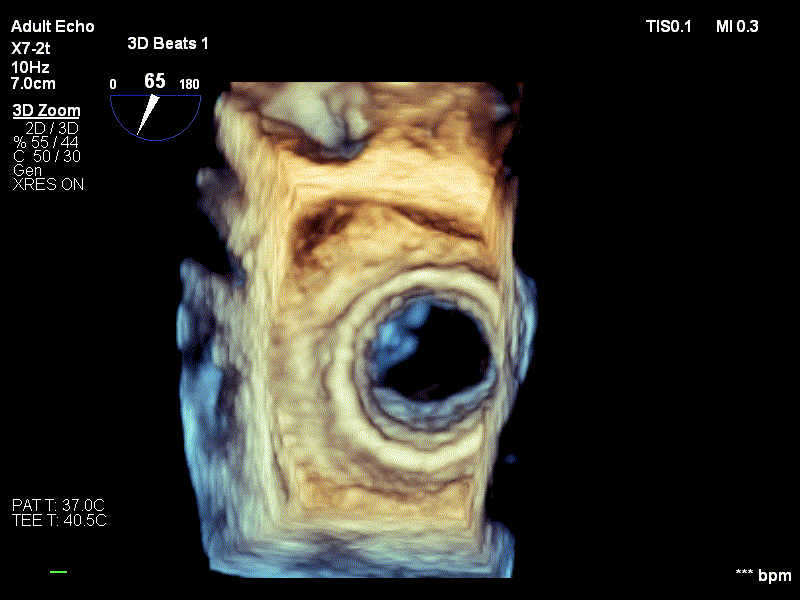

Diagnosticul de stenoză mitrală strânsă degenerativă a fost stabilit pe baza examenului ecocardiografic, realizat de dr. Irina Macovei-Dorobanțu, medicul cardiolog care s-a ocupat de pacienta pe toată durata spitalizării.

2. Imagine ecografie transesofagiană, valvă mitrală cu regurgitare minimă și stenoză semnificativă

3. Ecografie 3D valvă mitrală cu calcificări severe la nivelul cuspelor și al inelului, cu mobilitate mult diminuată